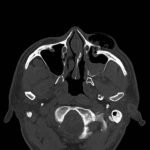

Physical exam showed marked left palpebral subcutaneous crepitus, as well as bulbar and palpebral conjunctival bulging. Visual acuity was normal with intact extraocular movements, and normal pupillary exam. Computed tomography (CT) imaging of the face was obtained and revealed multiple displaced fractures involving the left orbital floor and zygomatic arch associated with moderate periorbital and postseptal extraconal gas, resulting in orbital proptosis.